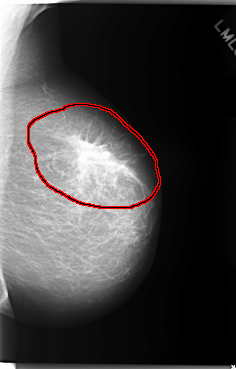

C_0081_1.LEFT_MLO

LEFT_MLO LINES 5904 PIXELS_PER_LINE 3768 BITS_PER_PIXEL 12 RESOLUTION 50 OVERLAY

FILE: C_0081_1.LEFT_MLO.OVERLAY

TOTAL_ABNORMALITIES 1

ABNORMALITY 1

LESION_TYPE MASS SHAPE IRREGULAR MARGINS SPICULATED

ASSESSMENT 5

SUBTLETY 5

PATHOLOGY MALIGNANT

TOTAL_OUTLINES 1

BOUNDARY